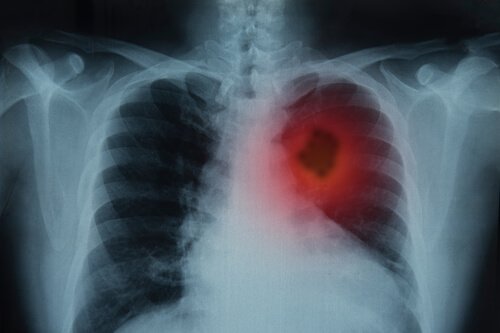

Als deze symptomen langer aanhouden dan drie weken dan is het van groot belang dat je je dokter bezoekt voor een röntgenfoto van de borstkas.

Op basis van je röntgenresultaten kan de arts dan je gedetailleerde medische geschiedenis opvragen en een lichamelijk onderzoek uitvoeren samen met andere laboratoriumtesten.

- Beeldvorming (zoals röntgenfoto’s): met deze procedure kan de arts beelden van de interne delen van je lichaam verkrijgen.